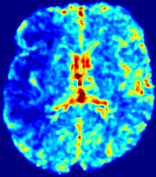

4.3.2 Diffusion Imaging via Advection-Diffusion

Slice #1Slice #2Slice #3Slice #4Slice #5Slice #6Dgtsuperscript𝐷gtD^{\text{gt}}Refer to captionRefer to captionRefer to captionRefer to captionRefer to captionRefer to captionDestsuperscript𝐷estD^{\text{est}}Refer to captionRefer to captionRefer to captionRefer to captionRefer to captionRefer to captionRefer to caption0.300.300.300.240.240.240.180.180.180.120.120.120.060.060.060.000.000.00(mm2/s)𝑚superscript𝑚2𝑠(mm^{2}/s)𝐕est𝟐subscriptnormsuperscript𝐕est2\|\bf{V}^{\text{est}}\|_{2}Refer to captionRefer to captionRefer to captionRefer to captionRefer to captionRefer to captionRefer to caption0.00300.00300.00300.00240.00240.00240.00180.00180.00180.00120.00120.00120.00060.00060.00060.00000.00000.0000(mm/s)𝑚𝑚𝑠(mm/s)

Figure 15: PIANO identifiability testing: diffusion imaging via advection-diffusion. Top row shows Dgtsuperscript𝐷gtD^{\text{gt}} used for simulating ground truth pure diffusion. Rows below show the estimated Destsuperscript𝐷estD^{\text{est}} and 𝐕est2subscriptnormsuperscript𝐕est2\|{\bf{V}}^{\text{est}}\|_{2} on corresponding slices. Note that the plotted value scale for 𝐕est2subscriptnormsuperscript𝐕est2\|{\bf{V}}^{\text{est}}\|_{2} is 0.01 of that for Dgtsuperscript𝐷gtD^{\text{gt}} and Destsuperscript𝐷estD^{\text{est}}.

Similarly, we test the behavior of PIANO when estimating both advection and diffusion from a pure diffusion-driven process. The goal is to determine if PIANO is able to recognize that there is only diffusion governing the given concentration time-series. We use the same ‘Diffusion Imaging’ data simulation of Sec. 4.2.1 as the concentration dataset, PIANO estimates both velocity 𝐕estsuperscript𝐕est{\bf{V}}^{\text{est}} and diffusivity Destsuperscript𝐷estD^{\text{est}}. Estimation results in Fig. 15 confirm PIANO’s identifiability again: the estimated 𝐕est2subscriptnormsuperscript𝐕est2\|{\bf{V}}^{\text{est}}\|_{2} is almost invisible compared to Destsuperscript𝐷estD^{\text{est}}, even plotted with a 1%percent11\% value range compared to that for Destsuperscript𝐷estD^{\text{est}}. On the other hand, Destsuperscript𝐷estD^{\text{est}} achieves comparable estimation performance as ‘Diffusion Imaging via Diffusion’ in which PIANO predicts Destsuperscript𝐷estD^{\text{est}} alone (shown in Fig. 13).